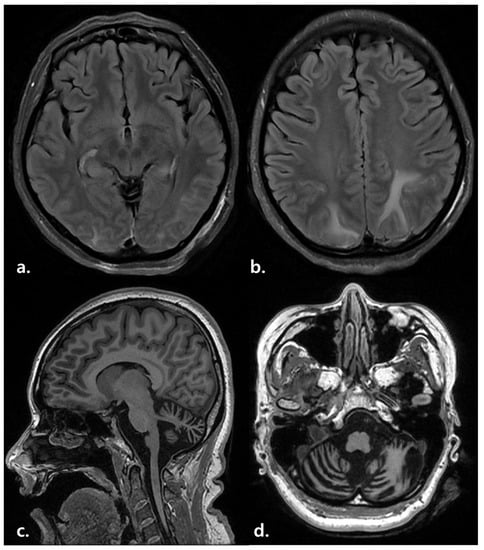

| 1 | 33 | F | Hypoxic brain injury | Admission (15 August 2021) | 0 | 0 | 0 | 5 | L-tube |

| RM transfer (30 September 2021) | 0 | 0 | 11 | 5 | Soft diet | ||||

| AC diagnosis (20 October 2021) | 3 | 5 | 17 | 4 | Regular diet | ||||